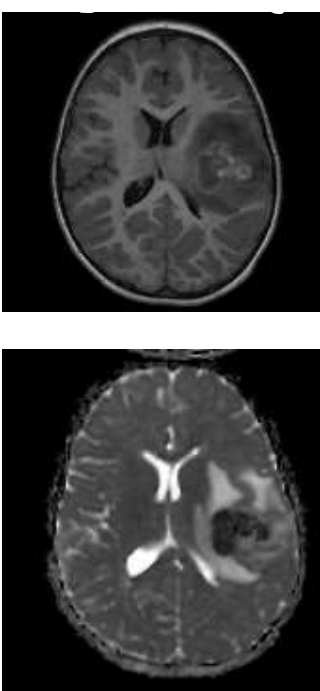

Sobre a lesão demonstrada no exame de ressonância magnética apresentado abaixo, assinale a alternativa que contenha o diagnóstico etiológico e a localização da lesão.